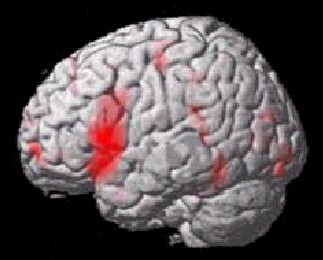

Visualisierung (SPM2)

• Render       Sections     Slices

Render

54

• new style old style